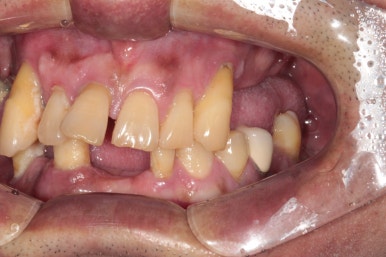

딱 봐도 치아가 많이 없으신 50대 남자 환자분입니다.

어떻게 그 동안 식사를 하셨는지 단번에 걱정이 되었던 분.. 개원 후 얼마 되지 않아 방문해셨던 분이라 더욱 기억에 남는 분입니다.

큰 어금니는 한개 밖에 남지 않았고, 그나마 작은 어금니도 여러개 소실되어 있네요.

아래 앞니도 없어졌고.....

그나마 큰 어금니가 한 개 남은 오른쪽 위 구강 내 사진입니다.